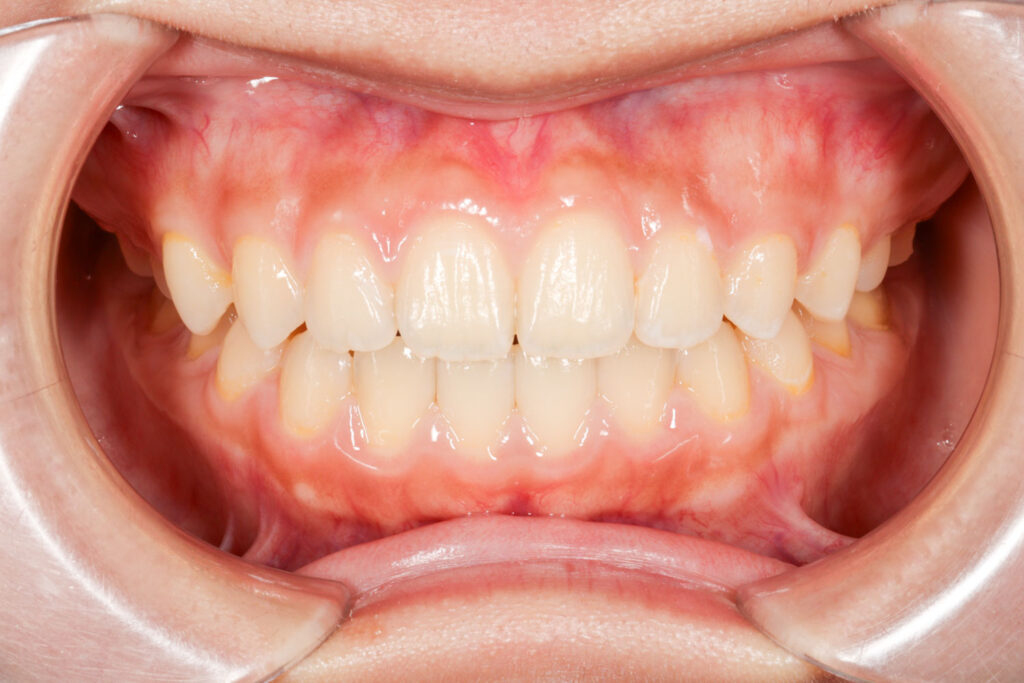

Before

年齢 10代

治療装置 上は裏側の矯正装置(ハーフリンガル)

治療内容 上下左右4本抜歯

治療期間 2年8か月

リスク 歯の移動に伴う痛み、歯肉退縮、歯根吸収、歯肉炎、虫歯

主訴 八重歯が気になる

症状 叢生(ガタガタ)

治療回数 33回程度

総額費用 125万円程度